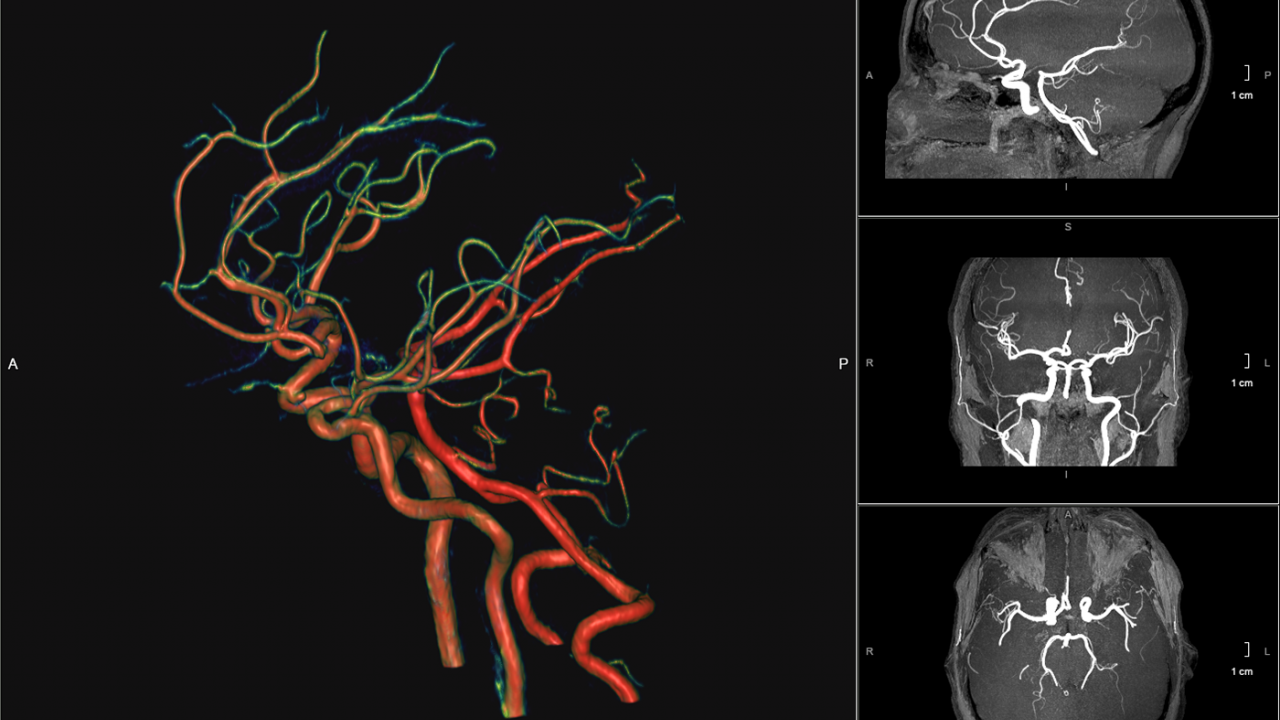

Interventional Neuroradiology – Los Angeles, CA | Cedars-Sinai。Division of Neuroradiology - Neuroradiology Division。Interventional Neuroradiology | American Radiology Associates。Interventional Neuroradiology: Strategies and Practical TechniquesConors and WojakJ・J・コナーズとジョアン・C・ヴォジャク#洋書#医学書#脳神経外科#脳血管内治療#脳血管解剖商品購入後のキャンセル、ATMコンビニ払いでの放置、受取評価の放置はメルカリ公式での迷惑行為です。Interventional Radiology: Fundamentals of Clinical Practice。購入はメルカリの規則を理解し、商品内容や説明を良く確認の上、ご購入をお願いいたします。救急救命士標準テキスト 改訂第11版 未開封新書。◾️amazonでの2024.12.7現在の価格は243$でした。アリの巣の生きもの図鑑。【商品状態】古い書籍で、ハードカバー書籍です。耳穴診療法 中国伝統医学 9784925181754。(薄いカバーも元来ありません)特筆すべき傷み・折れ • 落丁などありませんが標準範囲内での経年変化はございます、とくに本下面のページに僅かな汚れはありました。【まい子】数理統計学史。写真の如く、ページの角折れと、1箇所捺印が見られ、また裏表紙のうらに鉛筆にて記銘がありましたがこちらは消しゴムで消しています。ACLS 二次救命処置 プロバイダー マニュアル【裁断なし】。微かに痕跡あるかもしれません。ワンランク上のファーマネックス•ビジネス ニュースキン ハンドブック2。確認する限り、内部はマーカー引きや書き込みはなく良好な状態です。スペクトル法による数値計算入門。中は問題なく読める状態です。PALS プロバイダーマニュアル AHA 2020。確認を行いましたが、その他の書き込み等の見落としがあるかもしれませんご了承の上、ご購入下さい。【おん】青本⑤⑥⑧。【注意事項】個人保管の中古品です。骨移植 最近の進歩。使用感は人によって感じ方に差があります。タンパク質の構造入門 第2版。神経質な方のご購入はお控え下さい。心臓血管外科手術 周術期管理のすべて 2版。購入後のクレームは対応しかねます。美容外科医複数人監修美容鍼 MAOの美容鍼2023。上記をご理解頂ける方のご購入をお願いします。【バラ・まとめ売り】看護系・医療系の方向け教科書。【発送に関して】送料無料の匿名配送で対応致します。日本薬局方解説書。商品発送後にキャンセルを希望する場合は、往復送料および代引き手数料は、お客さまの負担となります。レビューブック 内科・外科 2022−2023年。【その他】喫煙者&ペットはなしの環境で管理しています。しし 筋膜系の機能解剖アトラス。◾️既にある程度の相場を見て出品しております。病院が見えるシリーズ15巻セット。値下げは考えておりません。太長寿で奇跡を起こせ!! : コリや疼痛で悩む人を解放する。夜間のコメントは返事が翌朝になります。【りんかページ】クエスチョン・バンクSelect必修など3冊。

• Interventional Neuroradiology – Los Angeles, CA | Cedars-Sinai

• Division of Neuroradiology - Neuroradiology Division

• Interventional Neuroradiology | American Radiology Associates

• Interventional Radiology: Fundamentals of Clinical Practice